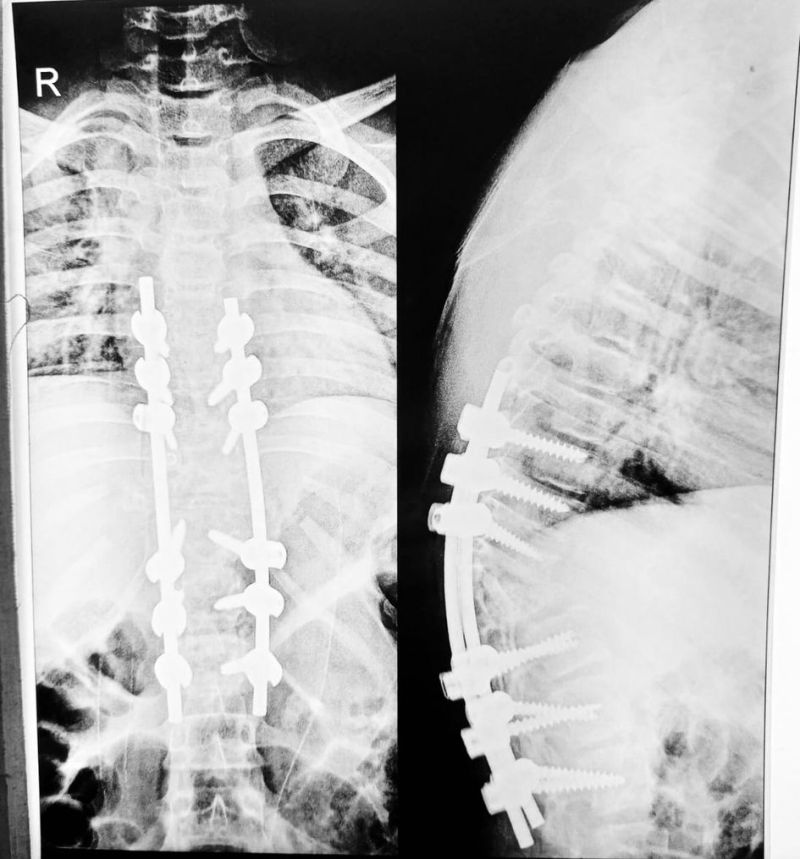

ऑर्थो सर्जन डॉ. हरि मेनन ने राजस्थान पत्रिका को बताया कि कृष्णा को कंजेनाइटल किफोसिस वीथ पेरा प्लेजिया बीमारी थी। किशोर के रीढ़ की हड्डी से गुजरने वाली नस दबने से पैर ने काम करना बंद कर दिया। यह समस्या लंबे समय तक रहती तो ऑपरेशन के बाद अच्छा परिणाम मिलना मुश्किल था। यह मामला 8 महीने पुराना था, इसलिए ऑपरेशन का निर्णय किया और उभार के सी आकार को कम करते हुए रीढ़ की हड्डी में नस पर पड़ रहे दबाव को कम किया गया। आमतौर पर प्राइवेट अस्पताल में ऐसे ऑपरेशन का खर्च 3 लाख से ज्यादा होता है, लेकिन सिविल अस्पताल में नि:शुल्क ऑपरेशन किया गया है। यह एक ऐसा ऑपरेशन था जिसमें मासूम बच्चे के साथ भावनाएं जुड़ी हुई थीं। उसे फिर से दौडऩे के लिए तैयार करना एक चुनौती थी।